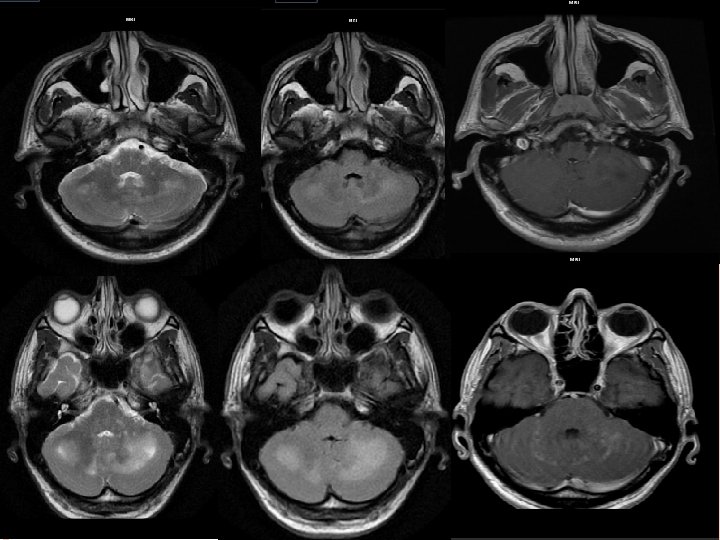

Depending on its stage of maturation tuberculoma’s appearance varies on MRI. Stages of tuberculoma: Non caseating Caseating with solid centre Caseating with liquid centre

NON CASEATING Hyperintense on. T 2 W images and slightly hypointense on T 1 W images with homogeneous post contrast enhancement.

CASEATING WITH SOLID CENTRE: Hypo to isointense on both T 1 W and T 2 W images with an iso to hyperintense rim on T 2 W images. In presence of an edema rim is inseparable on T 2 W images. Shows rim enhancement on post contrast T 1 W images.

CASEATING WITH LIQUID CENTRE: When the solid centre liquefies it appears hyperintense on T 2 W images with surrounding hypointensity. On post contrast images show rim enhancement.